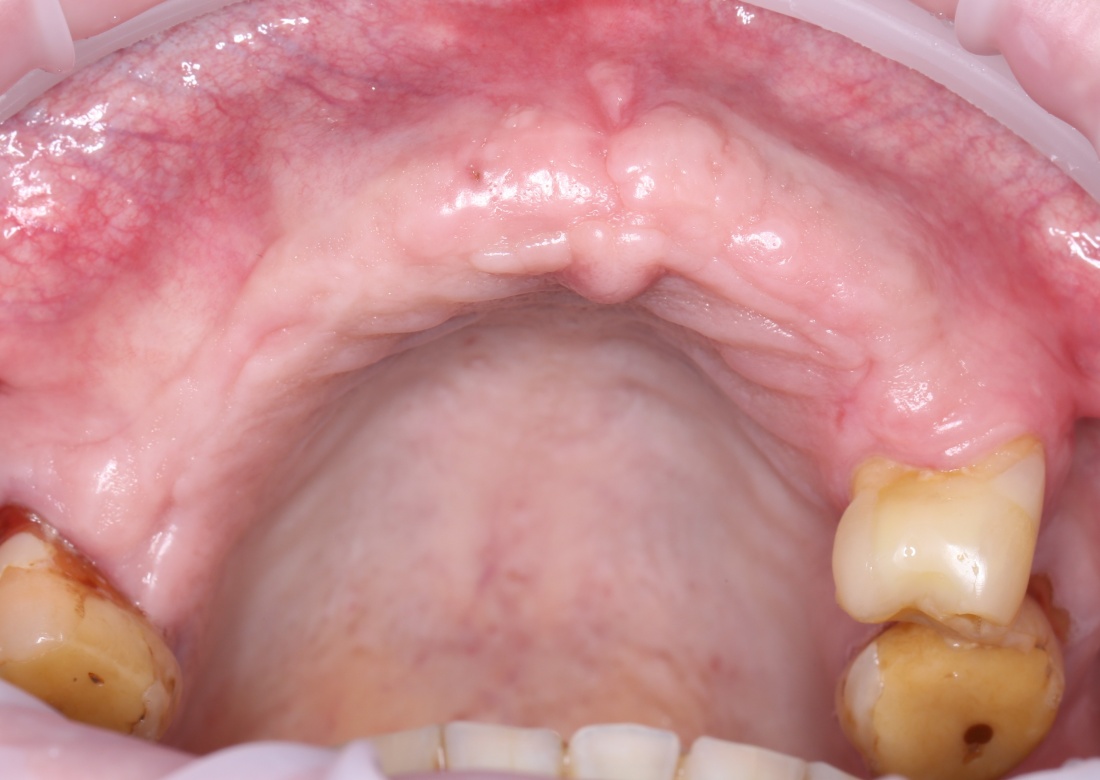

Показания

Зная плюсы и минусы, вы без труда сможете определить показания к остеопластической операции методом остеотомии. Это:

— вертикальная или горизонтальная атрофия костной ткани верхней или нижней челюстей, концевые или включённые дефекты.

— III или IX биотип костной ткани — идеальны. С I и II биотипом придётся повозиться

— минимально — 4-6 мм до смежных структур (нижнечелюстного нерва, верхнечелюстной пазухи, в вестибуло-оральном направлении и т. д.)

— хорошая оснащенность клиники, светлая голова и руки доктора, растущие не из жопы.